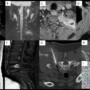

- A – Coronal STIR shows hyperintensity within the left transverse process of T1 vertebra and the posterior aspect of the left 1st rib with soft tissue extension.

- B – Coronal DWI showing diffusion restriction in corresponding areas.

- C and D – Postcontrast axial and coronal T1FS shows expansile lytic lesion with heterogenous enhancement, cortical erosion and soft tissue extension.•E – Sagittal T1 showing hypointenisty within posterior body of L5 vertebra.

- F – Postcontrast sagittal T1FS showing significant heterogenous enhancement of L5 vertebral body.

- G- Prone CT-guided biopsy of expansile lytic lesion in left 1st rib through a posterolateral approach

- H – Axial CT showing moth-eaten bone destruction in L5 vertebral body.